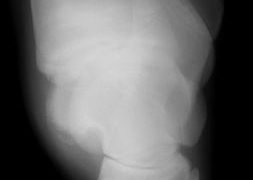

軟骨下骨嚢胞(Subchondral Bone Cysts) ~ 関節軟骨の深部に骨嚢胞を生じる疾患

軟骨下骨嚢胞(SBC)は、骨嚢胞とも呼ばれ、発育期整形外科的疾患の一種です。SBCは若い馬の跛行の重要な原因となっています。SBCは骨軟骨症の兆候であり、骨内の円形空洞からなり、関節面を含む場合も含まない場合もあります。関節が侵されている場...